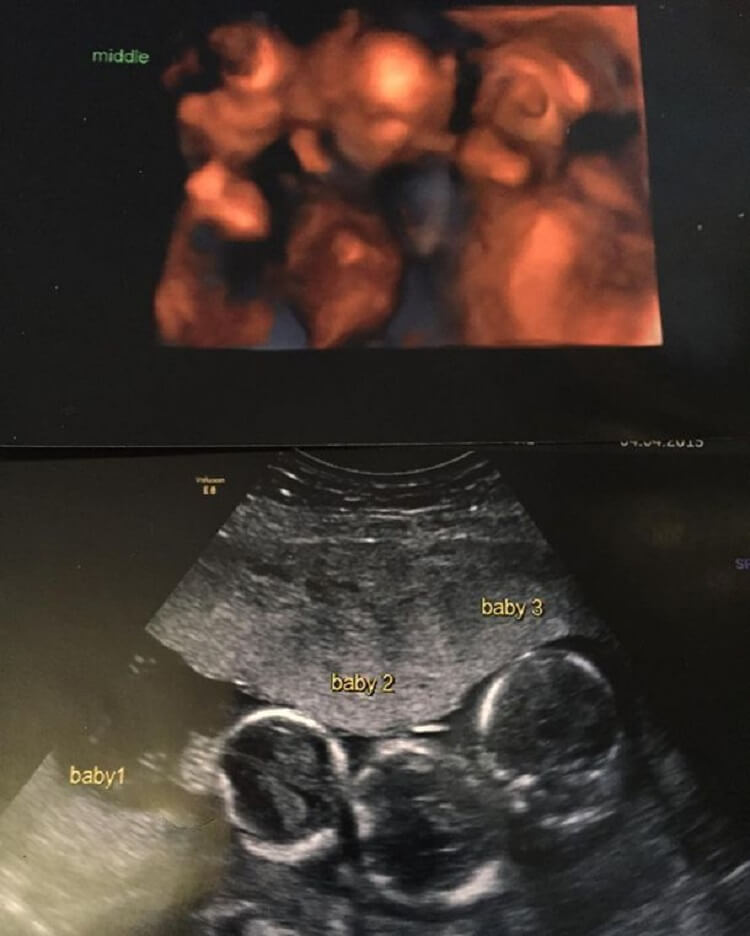

Но врач сообщила им новость, которая на мгновение просто выбила их из колеи. Бекки ожидала тройню: «Это была самая шокирующая новость в моей жизни. За всю историю наших семей в них никогда не было тройняшек — этого мы никак не ожидали».

С первых дней все стали замечать, что тройняшки выглядят абсолютно одинаковыми. Это было странно, поскольку врачи говорили родителям, что тройняшки рождаются разнояйцевыми и сильно отличаются друг от друга. Однако в этом случае даже родителям, которые обычно без труда различают близнецов, не всегда удавалось это сделать. Врачи предложили сделать анализ ДНК .

Результат удивил всех: оказалось, что трое мальчиков были однояйцевыми близнецами. Тройняшки из одной клетки — это редчайшее явление.